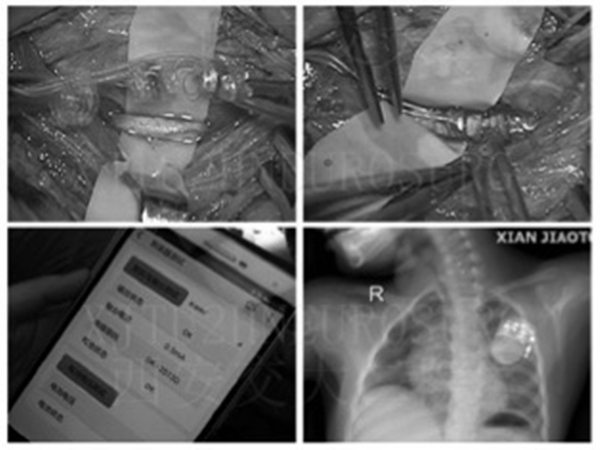

这名患儿出生后6个月就出现了抽搐发作,开始时发作的时间还比较短,大概持续5分钟左右,逐渐波及左下肢及右侧肢体,后来,经常遇到感染就发作,而且持续时间越来越长,最长的发作持续了3个小时。虽经药物治疗,但效果不佳,来我院后通过基因检测,诊断为“癫痫;Dravet综合征”。这种癫痫综合征往往属于药物难治性癫痫,于是在患儿对药物治疗不佳的情况下,开始了生酮饮食治疗,但2个多月前出现生酮饮食不耐受,在停用生酮饮食期间,患儿再次出现抽搐发作,多次因长时间发作收住ICU抢救。黄绍平教授带领的我院小儿神经专业团队对其进行了细致谨慎的评估,鉴于患儿发作频繁,且每次发作均表现为癫痫持续状态,持续时间长,对多种抗癫痫药物反应不佳,可行迷走神经刺激术。经过充分的术前准备,2018年11月26日,在手术麻醉科的协助下,神经外科吕健主任医师、王举波主治医师、权瑜主治医师为该患儿在全麻下施行了迷走神经刺激器植入术。术后患儿恢复顺利。2018 年12月 26日开机,起始电流强度为0.5mA,患儿无不良反应。开机后仅发作一次,持续2-3分钟,给予侧卧位后即缓解,之后未再发作。患儿父母对此疗效非常满意,于是便有了本文开始的一幕。